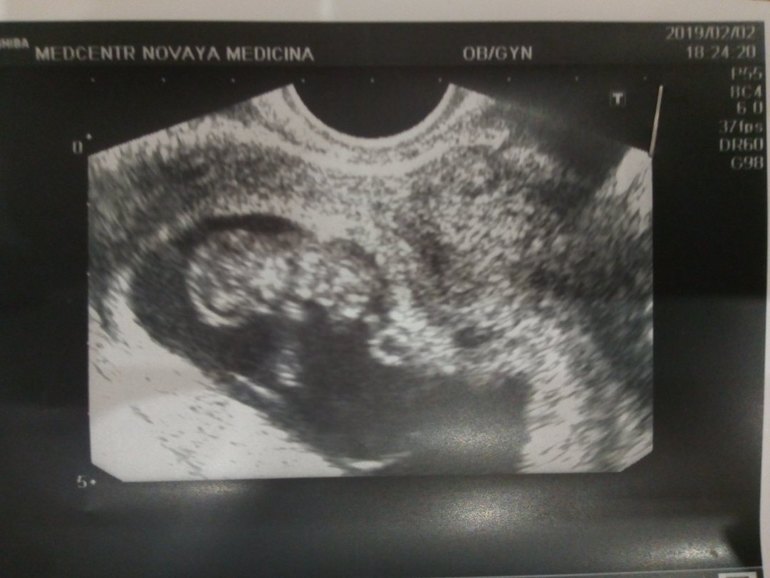

Всё о нашей беременностиДоброго всем дня. Прошел месяц почти после кровотечения, я и заболеть успела уже и на учет встать. А нам 9недель и 6 дней. В субботу заболел бок. В районе лобка, только правее, ровно на месте шва от операции, и раньше меня спайки беспокоили, но тут прям ноет и все. Вообщем пошли на узи. Все хорошо. Почти. Нижний край хориона перекрывает внутренний зев. Читала что поднимается со временем, да и врач узи сказала не паниковать. Но как не паниковать то ? Тут болит, тут тянет. А по узи ттттт все хорошо.

А вот и наша бусинка.